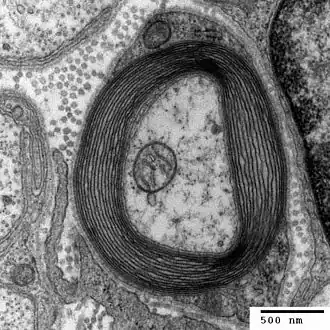

Myelin ist eine Biomembran, mit der die Axone der meisten Nervenzellen von Wirbeltieren umwickelt sind. Die so gebildete Myelinscheide erhöht die Geschwindigkeit der Erregungsleitung erheblich über die eines nackten Axons. Im Vergleich zu anderen Biomembranen weist Myelin einen besonders hohen Lipidgehalt (70 %) und einen relativ geringen Proteinanteil (30 %)[1] auf. Daher erscheint Myelin in der makroskopischen Sicht weiß, weshalb stark myelinisierte Regionen im Zentralnervensystem auch als „weiße Substanz“ bezeichnet werden, im Gegensatz zur gering myelinisierten „grauen Substanz“. Auch die schnell leitenden sensorischen und motorischen Axone des peripheren Nervensystems sind myelinisiert.

Myelin wird von Zellen gebildet: im Zentralnervensystem von Oligodendrozyten, im peripheren Nervensystem von Schwann-Zellen. Dass zentralnervöses Myelin von zellulären Fortsätzen der Oligodendrozyten gebildet wird, war lange umstritten und wurde erstmals 1962 von Mary Bartlett Bunge (1931–2024) und Richard P. Bunge (1932–1996) in elektronenmikroskopischen Aufnahmen gezeigt. Myelin wird häufig als ein spezielles Merkmal der Wirbeltiere angesehen. Allerdings besitzen einige wirbellose Tiergruppen funktionale und strukturelle Analogien.